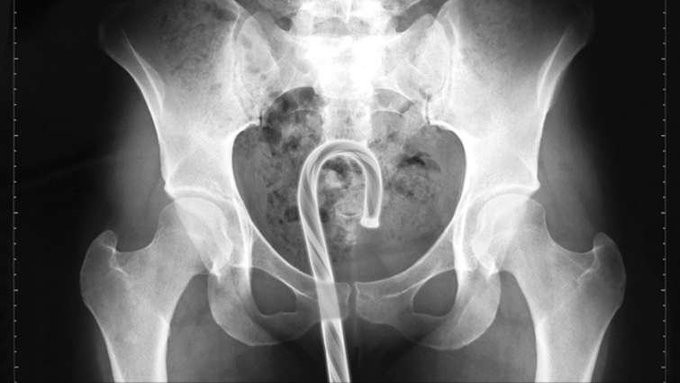

Одним из лидеров недели в Twitter стал хештег #WeirdThingsToPutUpYourAss (Странные штуки, которые суют в задницу). Проктологи со всего мира поделились рентгеновскими снимками содержимого анусов своих пациентов. Выяснилось, что огурец - еще не самое удивительно, что можно обнаружить там, где не светит солнце.